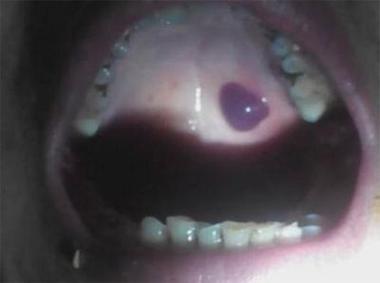

(图片来源网络,侵删)